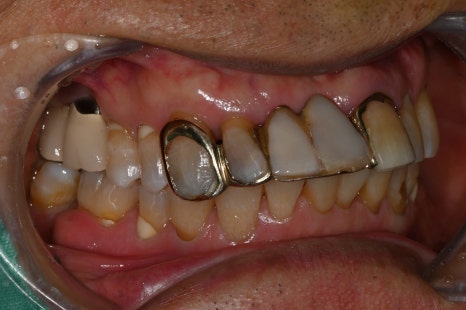

but also by gum inflammation or periodontal disease. In one case, a 70-year-old male patient visited the clinic with pain in the lower right

molar, and the examination revealed both periodontitis and

gum inflammation.

In this patient’s case as well, tartar removal and

periodontal treatment were performed first.